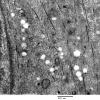

Hypoxia-Ischemia, fetal-neonatal

White Matter (5)